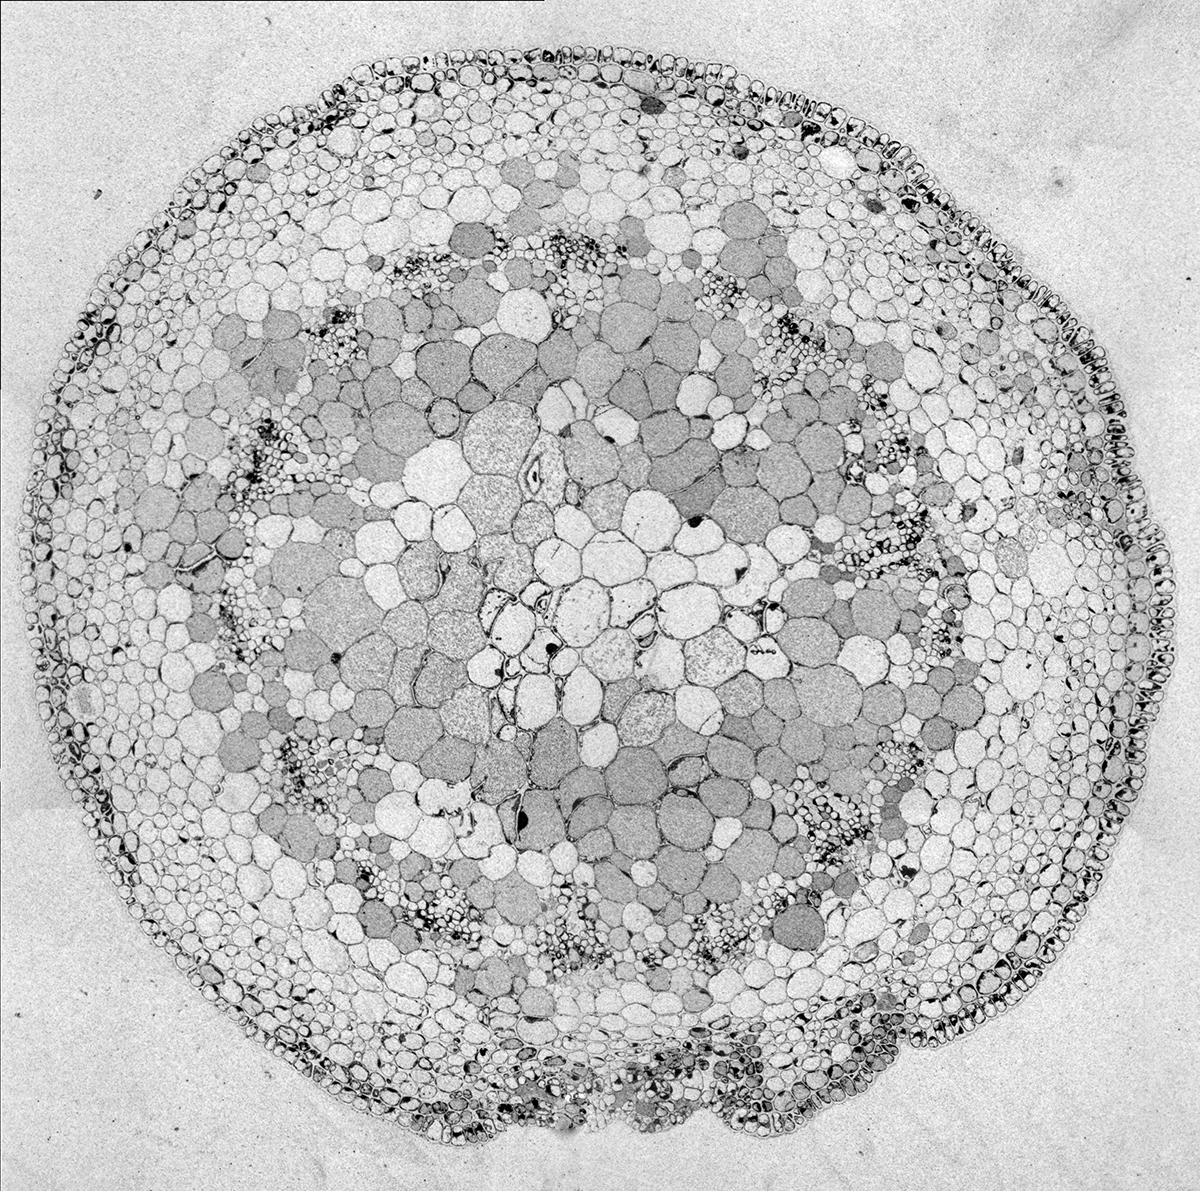

Retinal Ganglion Cells